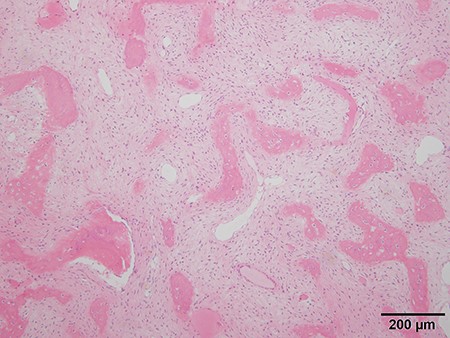

Because differential diagnoses included malignant transformation from fibrous dysplasia based on the clinical course and imaging, a CT-guided biopsy was performed. Tissue was obtained from various areas with differing contrast effect on MRI. Despite no histological evidence of malignancy, signs of fibrous dysplasia such as irregular osseous trabeculae of immature bone with no osteoblastic rimming were observed. Accounting for possibly insufficient samples, incisional biopsies of the right seventh and ninth ribs were performed. The results showed fibrous dysplasia signs similar to those that were shown by the CT-guided biopsy, and the patient was preoperatively diagnosed as fibrous dysplasia (Fig. 5).

Histologic analysis of the biopsy shows characteristics of fibrous dysplasia with irregular osseous trabeculae of immature bone with no osteoblastic rimming.

An enlarged lesion of fibrous dysplasia after bone maturation may suggest malignant transformation. Fibrous dysplasia undergoing malignant transformation often presents with hyper alkaline phosphatemia, and plain radiography or CT often reveal osteolysis or disruption of the cortex [3]. Fluorodeoxyglucose-positron emission tomography/computed tomography (FDG-PET/CT) is reportedly useful for differentiating fibrous dysplasia from metastatic bone tumors and for its early diagnosis of malignant transformation [4]. Our patient presented with hyper alkaline phosphatemia, and CT revealed an extra-osseous mass with cortical bone destruction and calcification. FDG-PET/CT showed strong abnormal accumulation. Furthermore, malignant transformation to low-grade sarcoma was suspected due to the continued growth of the lesion. However, diagnostic imaging for malignant transformation has been reported to cause false-positive results [5, 6]. Therefore, we performed multiple preoperative CT-guided needle biopsies and incision biopsies from multiple sites to confirm that there were no malignant pathological findings before surgery. No malignant findings were found in the final pathological diagnosis of the resected specimen.